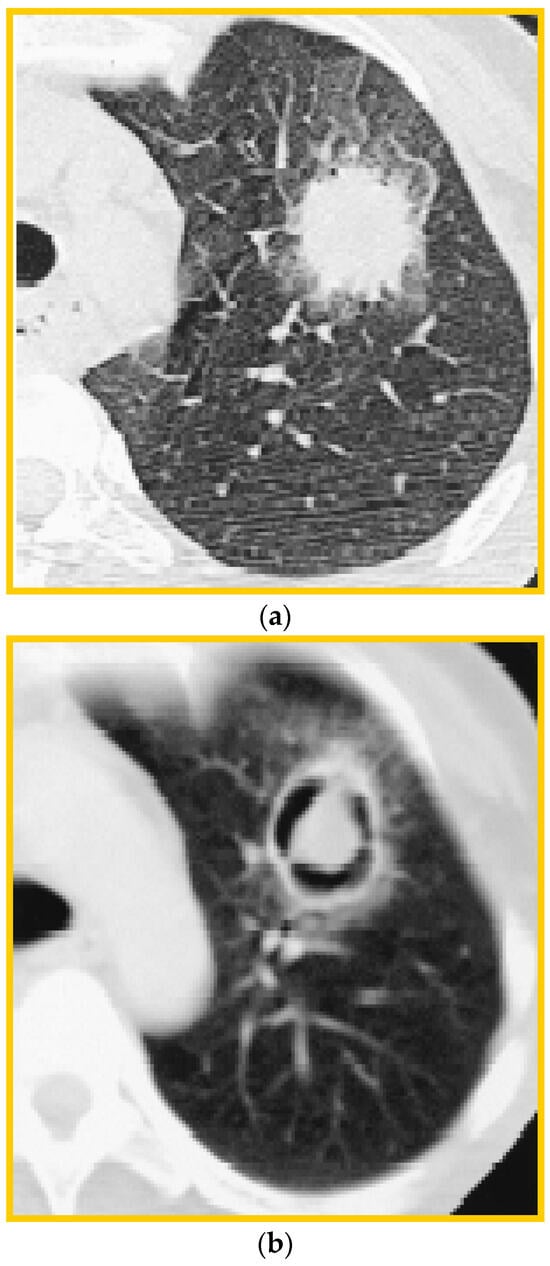

6. Imaging

- Kuhlman, J.E.; Fishman, E.K.; Burch, P.A.; Karp, J.E.; Zerhouni, E.A.; Siegelman, S.S. CT of invasive pulmonary aspergillosis. AJR Am. J. Roentgenol. 1988, 150, 1015–1020. [Google Scholar] [CrossRef] [PubMed]

- Alexander, B.D.; Lamoth, F.; Heussel, C.P.; Prokop, C.S.; Desai, S.R.; Morrissey, C.O.; Baddley, J.W. Guidance on Imaging for Invasive Pulmonary Aspergillosis and Mucormycosis: From the Imaging Working Group for the Revision and Update of the Consensus Definitions of Fungal Disease from the EORTC/MSGERC. Clin. Infect. Dis. 2021, 72 (Suppl. S2), S79–S88. [Google Scholar] [CrossRef] [PubMed]

- Greene, R.E.; Schlamm, H.T.; Oestmann, J.W.; Stark, P.; Durand, C.; Lortholary, O.; Wingard, J.R.; Herbrecht, R.; Ribaud, P.; Patterson, T.F.; et al. Imaging findings in acute invasive pulmonary aspergillosis: Clinical significance of the halo sign. Clin. Infect. Dis. 2007, 44, 373–379. [Google Scholar] [CrossRef] [PubMed]

- Greene, R. The radiological spectrum of pulmonary aspergillosis. Med. Mycol. 2005, 43 (Suppl. S1), S147–S154. [Google Scholar] [CrossRef] [PubMed]

- Desoubeaux, G.; Bailly, É.; Chandenier, J. Diagnosis of invasive pulmonary aspergillosis: Updates and recommendations. Med. Mal. Infect. 2014, 44, 89–101. [Google Scholar] [CrossRef] [PubMed]

- Park, S.Y.; Lim, C.; Lee, S.O.; Choi, S.H.; Kim, Y.S.; Woo, J.H.; Song, J.W.; Kim, M.Y.; Chae, E.J.; Do, K.H.; et al. Computed tomography findings in invasive pulmonary aspergillosis in non-neutropenic transplant recipients and neutropenic patients, and their prognostic value. J. Infect. 2011, 63, 447–456. [Google Scholar] [CrossRef] [PubMed]